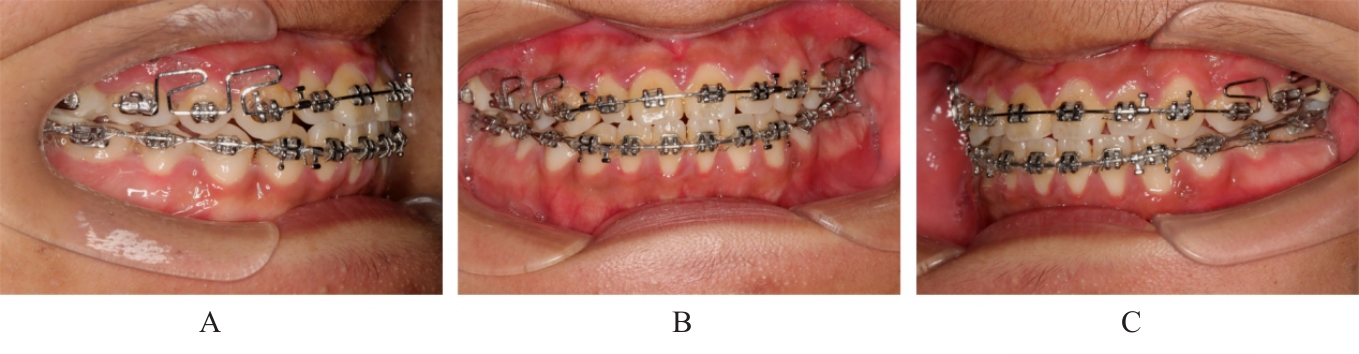

Grade Ⅲ open bite complicated with tongue hypertrophy treated by mandibular incisor extraction:A case report and literature review

Lei TIAN,Yuyan LIU,Yuqing WANG,Zhiyu ZHANG,Xiumei SUN( )

- Department of Orthodontics,Stomatology Hospital,Jilin University,Changchun 130021,China